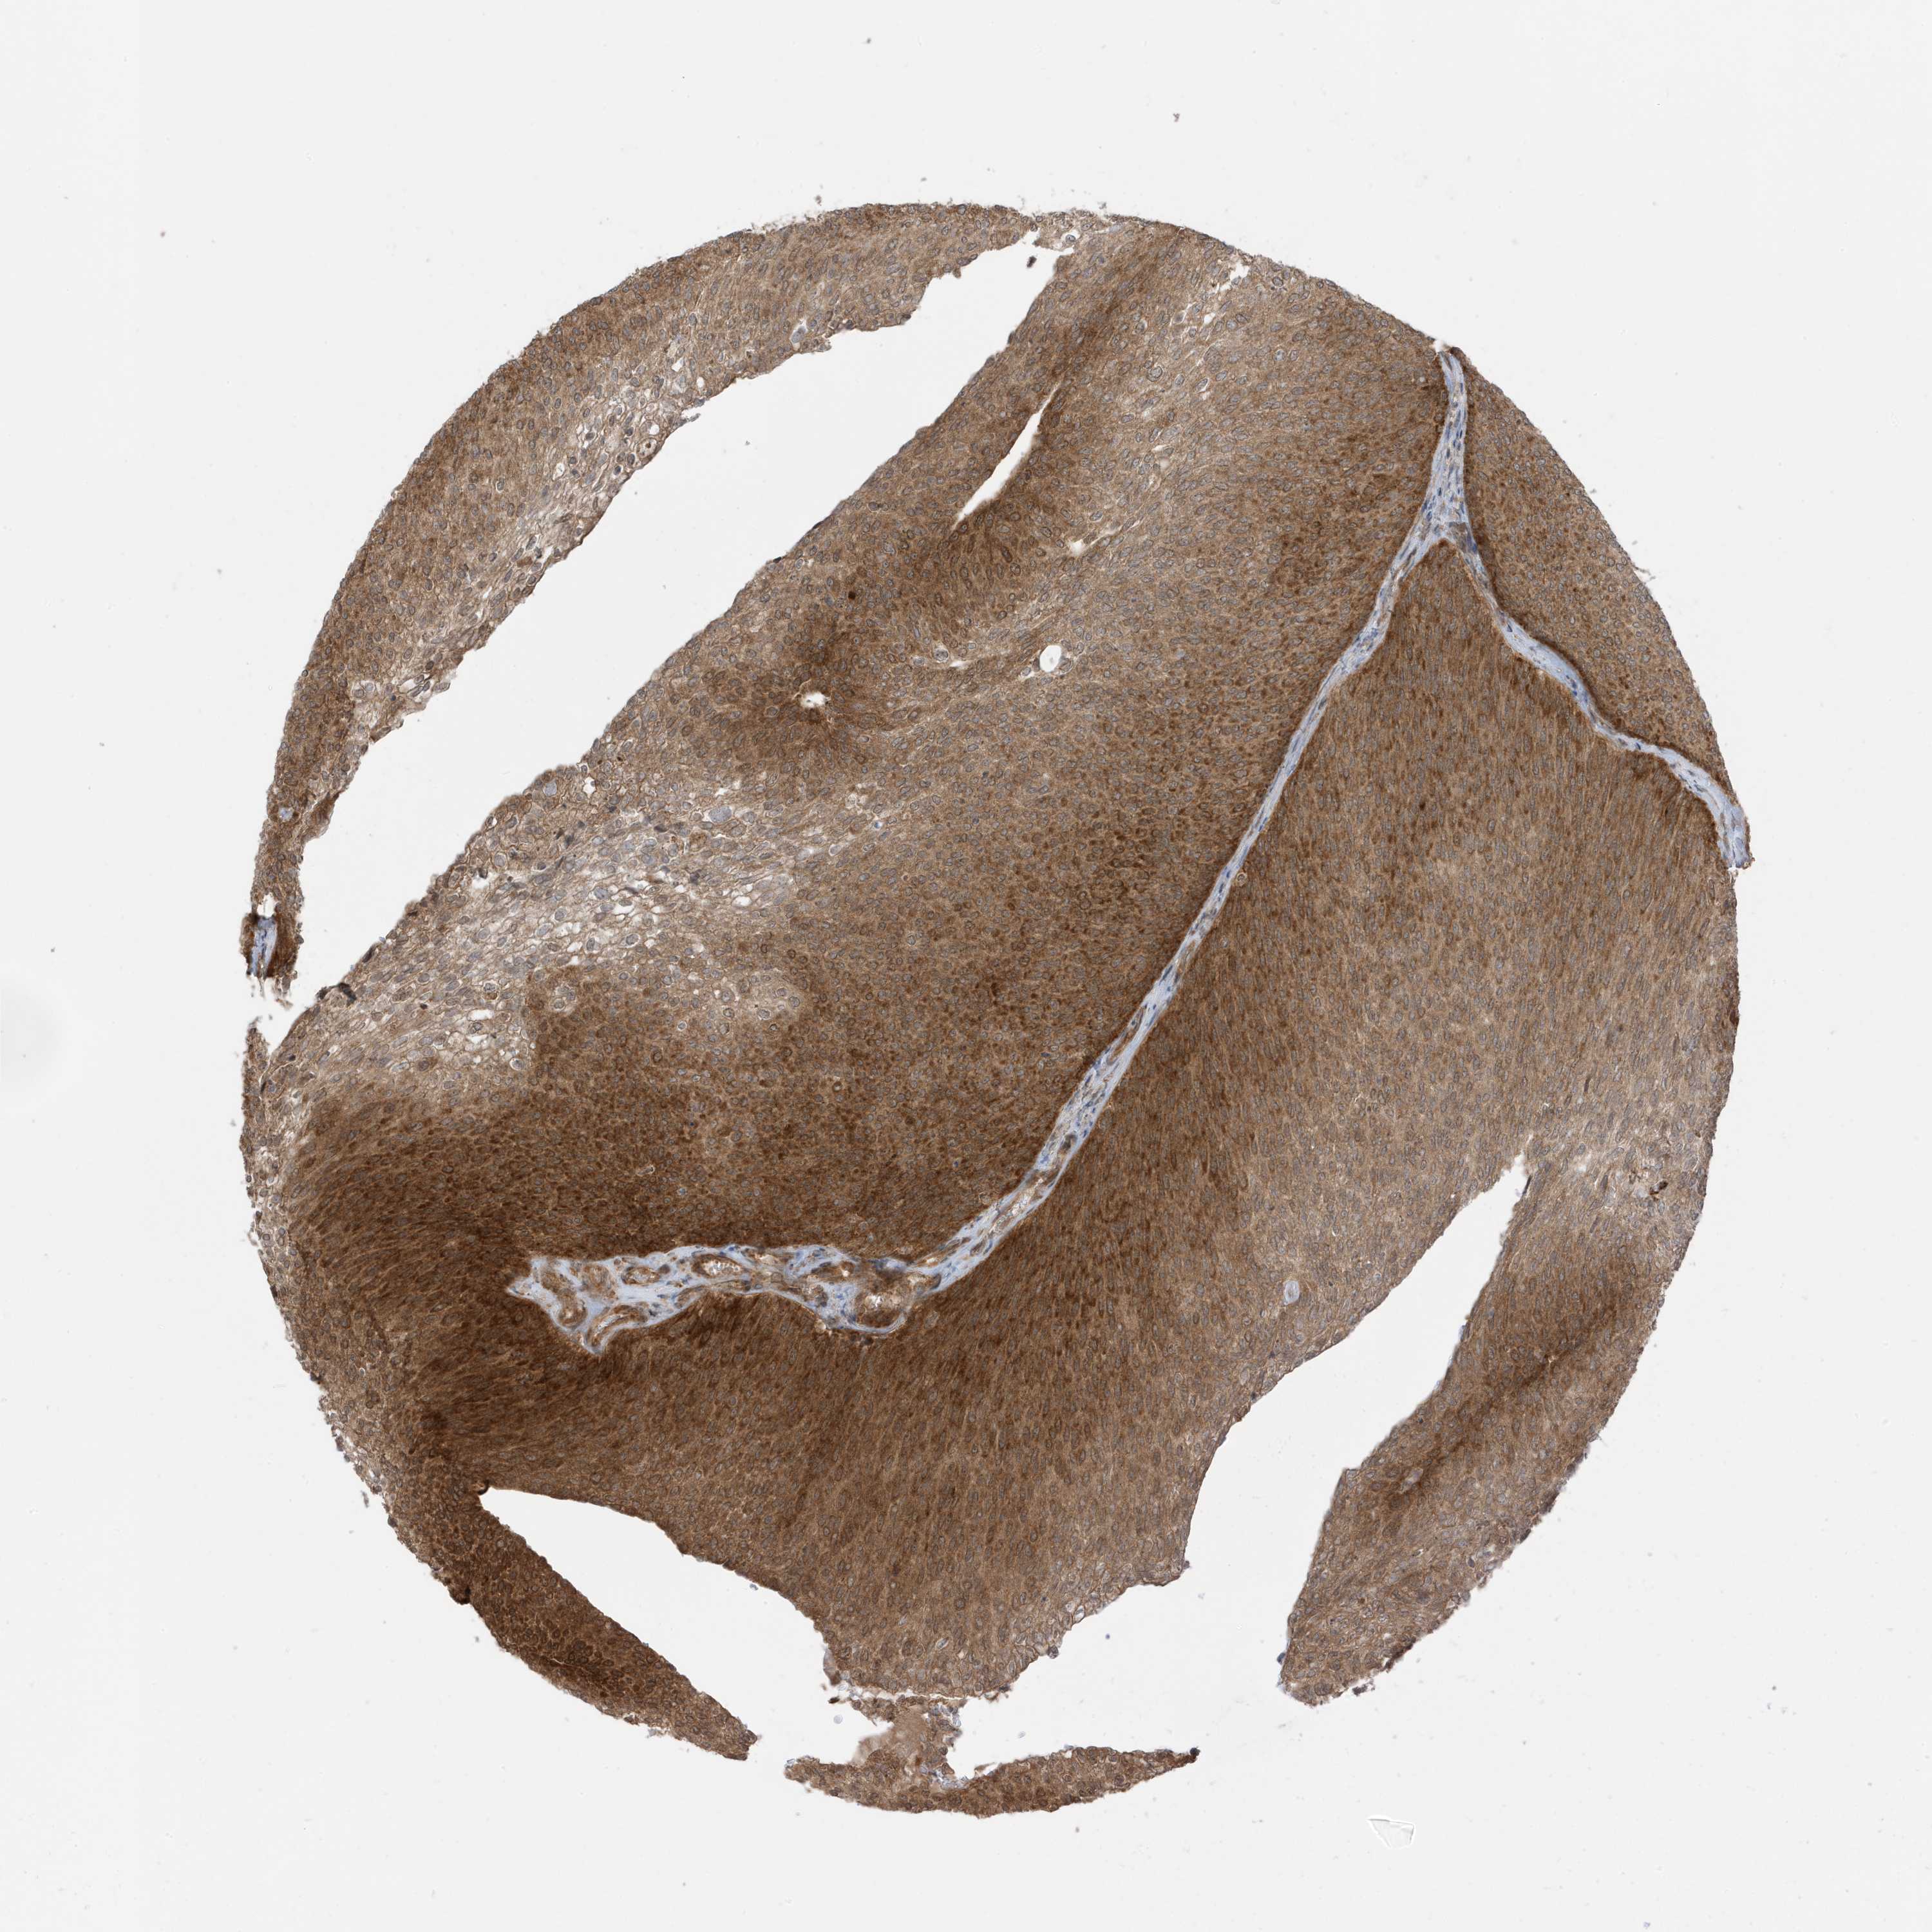

UROTHELIAL CANCER - Protein expressioni

A mouse-over function shows sample information and annotation data. Click on an image to view it in a full screen mode. Samples can be filtered based on level of antibody staining by selecting one or several of the following categories: high, medium, low and not detected. The assay and annotation is described here.

Antibody stainingi

Antibody staining in the annotated cell types in the current human tissue is reported as not detected, low, medium, or high, based on conventional immunohistochemistry profiling in selected tissues. This score is based on the combination of the staining intensity and fraction of stained cells.

Each image is clickable and will lead to virtual microscopy that enables deeper exploration of all samples and also displays staining intensity scores, fraction scores and subcellular localization as well as patient and tissue information for each sample.

Antibody HPA035399

Staining

High

Medium

Low

Not detected

Intensity

Strong

Moderate

Weak

Negative

Quantity

>75%

75%-25%

<25%

None

Location

Nuclear

Cytoplasmic/membranous

Cytoplasmic/membranous,nuclear

Urothelial carcinoma, Low grade

Urothelial carcinoma, High grade